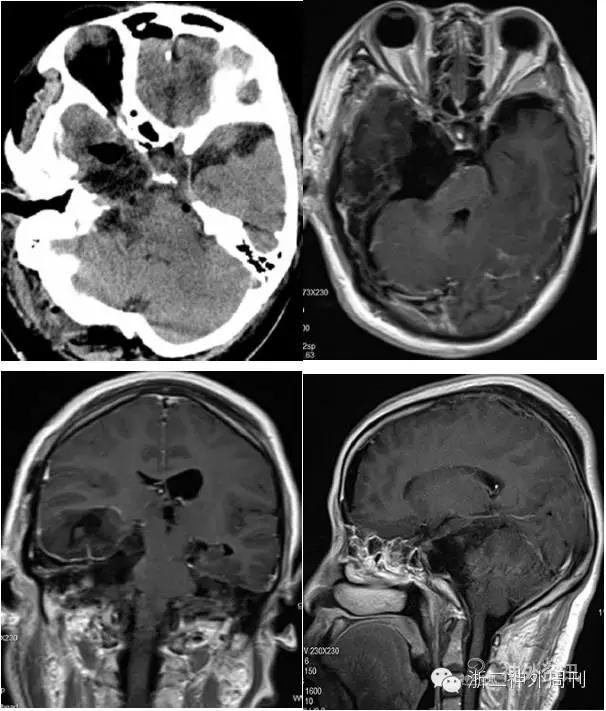

科室术前讨论,考虑肿瘤为良性,性质神经鞘瘤考虑,脑膜瘤待排。完善相关术前检查后,行右颞下经天幕入路肿瘤切除术,术中抬起颞叶,切开小脑幕,幕下见肿瘤组织,黄色,血供一般,质韧,内部见蛋壳样钙化及陈旧出血(图4)。仔细分离,全切肿瘤。

图4. 术中见黄色肿瘤组织,陈旧出血及蛋壳样钙化。

术后患者右颜面部麻木症状略好转,无其他神经功能影响,恢复良好,顺利出院。术后复查头颅CT及MRI增强显示肿瘤全切满意(图6)。

图6. 术后头颅CT及MR增强显示肿瘤全切。